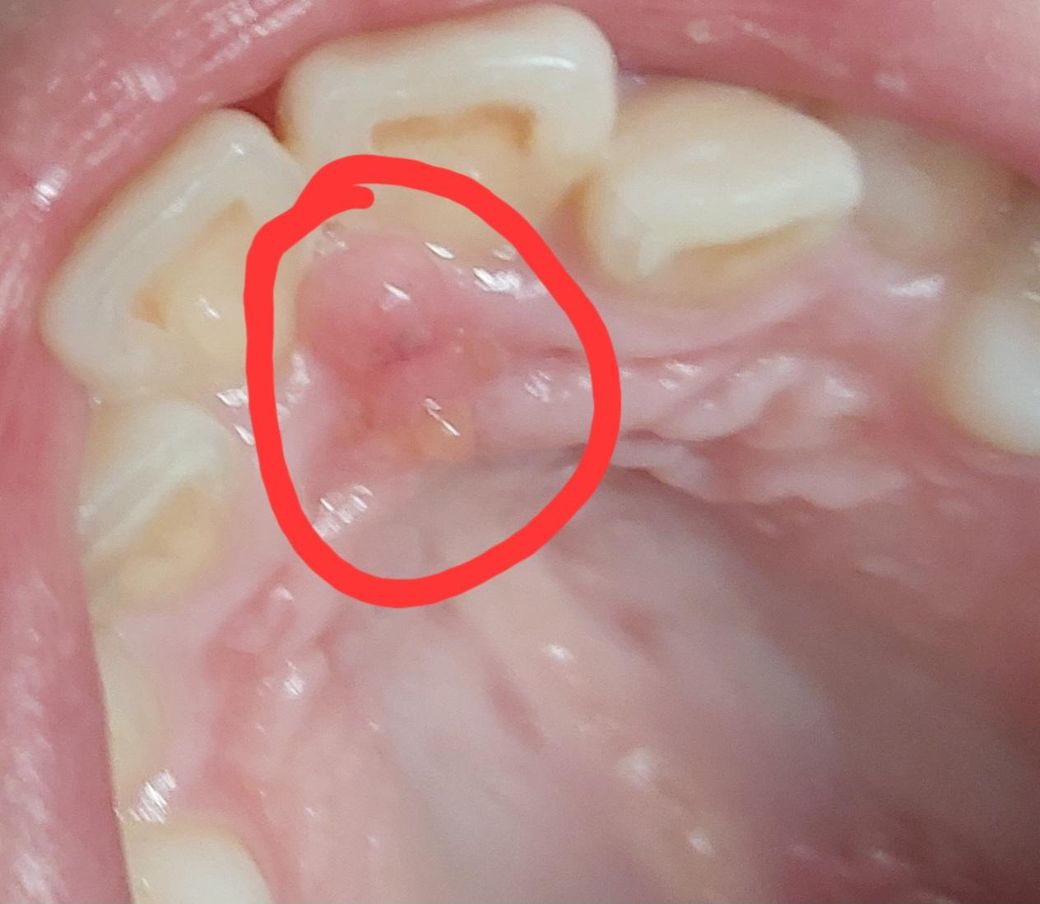

입천장 앞니 안쪽이 부어있어서 아파요

사진처럼

입천장 앞니 안쪽이 부었어요

거울로 비춰보니 고름이 생긴것같고

얼갱이가 아래위로 두개 부어있는데

• 1번 째 사진

입천장에 고름이 있는 것이 확인이 됩니다. 치과로 내원하여 치료 받으셔야할 것 같습니다.

2. 주변 치아 신경에서 비롯된 염증이거나 아니면 해당 부위 잇몸과 관련된 염증일 것 같습니다.

3. 만약 치아에서 비롯되었다면 신경치료, 잇몸과 관련되었다면 스케일링, 잇몸처치, 항생제 처방 등이 이뤄지겠습니다.

치아 주위 조직에 염증이 생겨 부기와 고름이 발생한 치주염 및 치근당 농양으로 의심이 되기에 치과진료를 받길 권합니다.